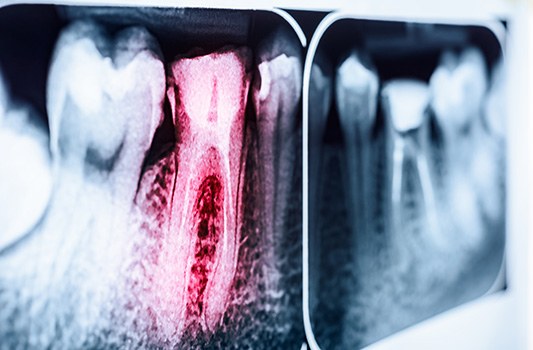

What Is Root Canal Retreatment?

As the name implies, root canal retreatment is a procedure that is performed on a tooth that has already received root canal therapy. It is often the best chance for saving your tooth in situations where the initial root canal has failed. We may recommend root canal retreatment if you are experiencing pain in the tooth in question or if there are any other signs that there’s a new issue that needs to be addressed.